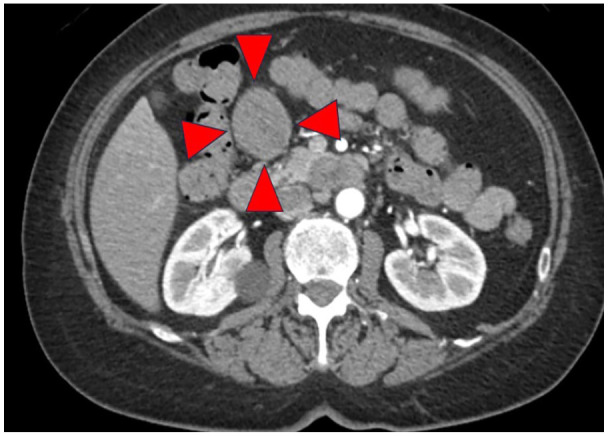

Neuroendocrine cells are distributed throughout the body's organs, though neuroendocrine neoplasms are primarily documented in the gastrointestinal tract and pancreas, with rare occurrences elsewhere. Herein, we report a case of primary neuroendocrine tumor of the omentum (omental NET) that was incidentally detected as an omental mass during preoperative screening for colorectal cancer. The patient, a 66-year-old woman, with abdominal pain and decreased oral intake, leading to a diagnosis of obstructive colorectal cancer with a large, 55 mm, mass around the gastropyloric region, which was discontinuous with the gastrointestinal tract. After the placement of a colonic stent at the site of the ascending colon cancer to decompress the colon, a laparoscopic right hemicolectomy was performed, simultaneously excising the mass. Postoperative pathology revealed a neuroendocrine tumor (NET). Subsequent examinations detected no other lesions of suspected primary disease and postoperative somatostatin scintigraphy found no other lesions, establishing a diagnosis of omental NET. The rarity of omental NETs is attributable to the absence of neuroendocrine cells in the omentum. Moreover, solid tumors originating primarily from the omentum are very rare, making preoperative diagnosis difficult; therefore, postoperative pathology should be utilized. We presented a very rare case of omental NET, previously reported only once in the literature, and believe that complete resection with minimal invasiveness should be performed for treatment of this malignancy. In addition, we emphasize the need for continued patient follow-up.

Abstract Image